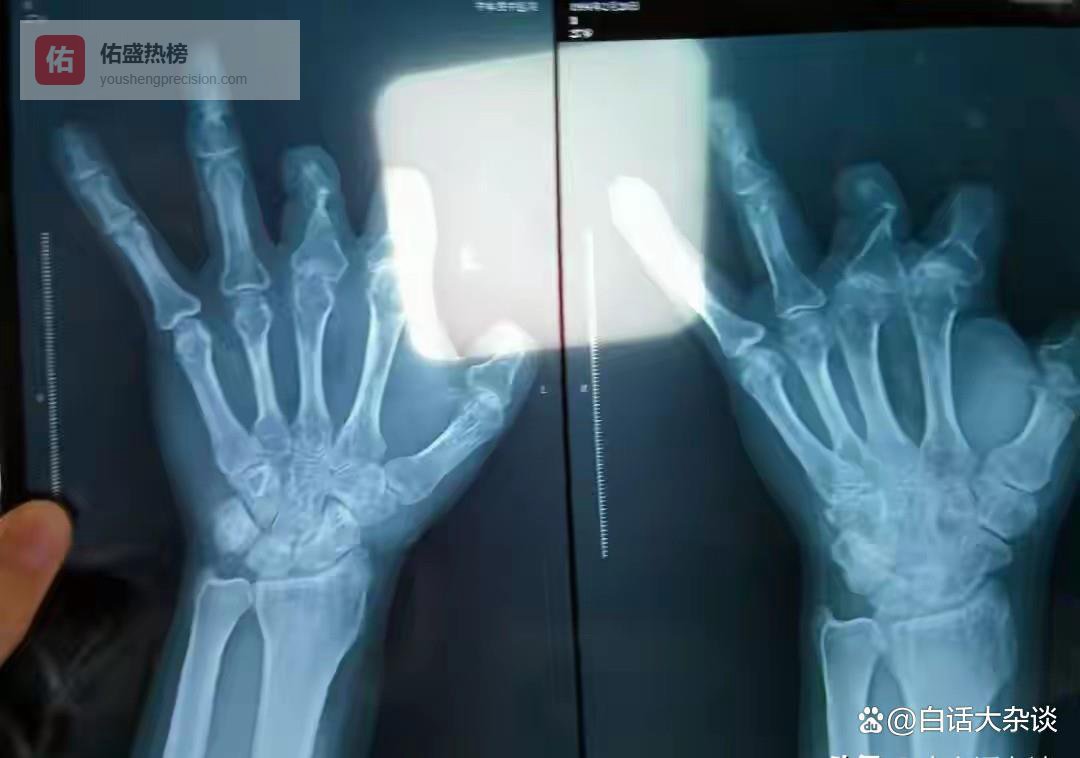

假把戏被戳穿三年后,也就是2021年,木工王师傅去其它医院复查拍X片时,却被影像师告知未发现该装置。

但是王师傅不再相王福建的说法,因为影像师明确告诉他,微血管吻合装置上的铁钉是不可能被吸收的,所以就直接报了警。

还有彭先生因为手术做的不满意,到其它医院拍X光时也没有检查到相关装置。

也就是说,王师傅和彭先生花高价安装的吻合装置,其实根本就不存在。

为啥要把手指患者安装的吻合装置认定为诈骗呢?原来这类吻合装置根本就无法用于手指手术中。

据了解,微血管吻合装置主要用于胳膊、大腿、手掌等部位手术,由于手指血管非常细,因此不适合使用这类装置。

令人震惊的是,报道还称王福建遭到投诉后,并没有收敛,为了防止患者拍X光,干脆在旁边组织中埋一个不适用的吻合装置,以避免投诉。